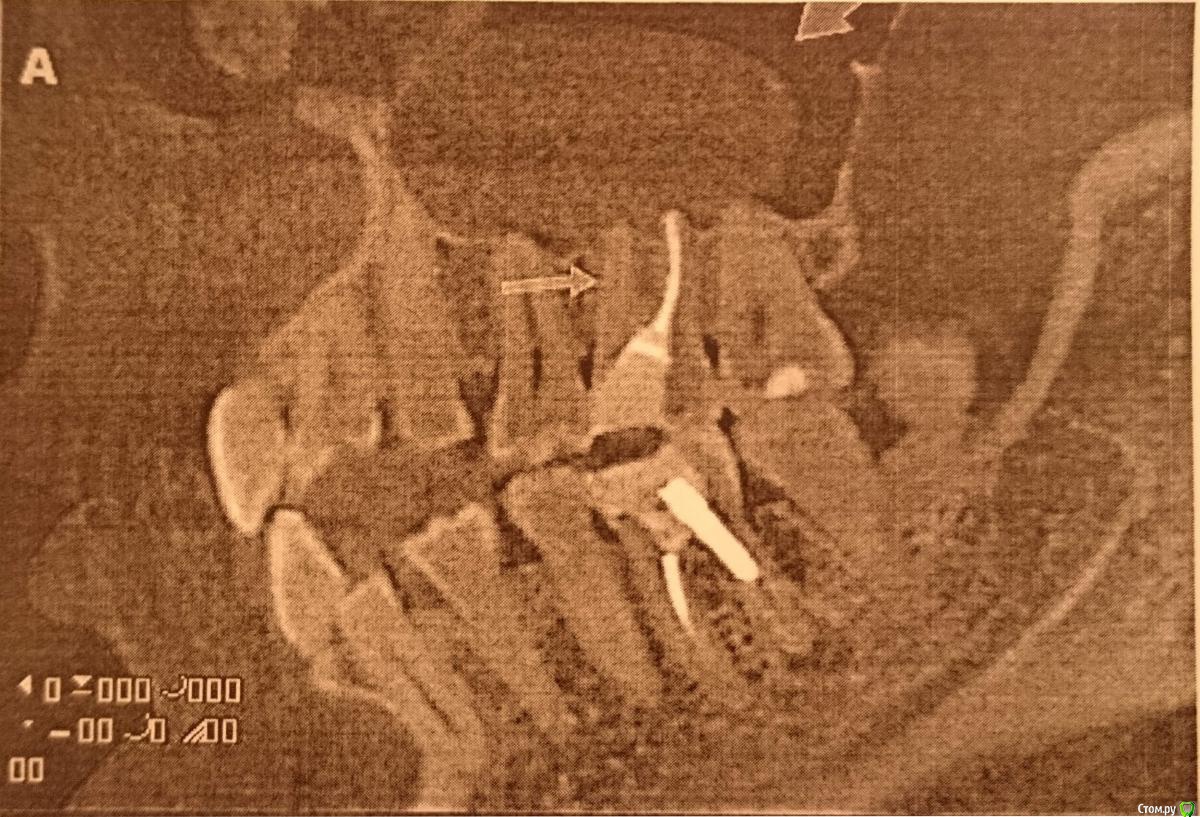

Rina753 Опубликовано 12 декабря, 2016 Поделиться Опубликовано 12 декабря, 2016 Здравствуйте.Киста корня зуба разраслась в кисту гайморовой пазухи. Выделяется гной из пазухи в носоглотку. Киста выявлена на кт.На данный момент хотелось бы провести лечение всего этого. Каким образом проводится и с чего начать? С уважением, Ирина Ссылка на комментарий

Гарриевич Опубликовано 12 декабря, 2016 Поделиться Опубликовано 12 декабря, 2016 Начните с лечения 6 зуба, так как по Кт он является возможной причиной процесса Ссылка на комментарий

wladdX Опубликовано 13 декабря, 2016 Поделиться Опубликовано 13 декабря, 2016 Несколько скриншотов. Ссылка на комментарий